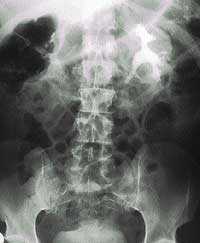

Заболеваемость циститом у женщин выше, прежде всего из-за близости отверстия уретры к влагалищу и перианальной области (рис. 1). Факторы риска развития ИМП у женщин включают фекальное загрязнение, малое потребление жидкости, использование спермицидов, частую смену полового партнера, беременность, менопаузу, низкий рН мочи, сухость слизистой оболочки влагалища, нейрогенный мочевой пузырь, болезни почек, урологические анатомические аномалии, иммуносупрессию, госпитализацию и последующую катетеризацию, нефролитиаз и сахарный диабет [6]. ИМП встречаются у мужчин реже, чем у женщин, вследствие анатомических особенностей мужской уретры. Частота ИМП становится одинаковой у мужчин и женщин в возрасте около 65 лет с учетом увеличения доли мужчин с доброкачественной гиперплазией предстательной железы [11]. Приблизительно 1/5 часть мужчин в возрасте старше 70 лет перенесла ИМП. Другими факторами риска для мужчин являются урологические нарушения, нейрогенный мочевой пузырь, госпитализация и дальнейшая катетеризация, иммуносупрессия [6]. Состояния с подавленным иммунитетом у мужчин и женщин включают возраст, диабет, рассеянный склероз, ВИЧ и другие хронические заболевания, которые могут нарушать иммунную систему. Среди пациентов с диабетом риск ИМП выше у женщин, чем у мужчин. Пациенты, страдающие диабетом, как правило, имеют в 2-4 раза большую частоту бактериурии, что приводит к более высокой частоте возникновения пиелонефрита.

![Рис. 1. Патогенез цистита у женщин [3]](/pimg3/infektsii-mochevivodyashix-putey-4A20C.png)